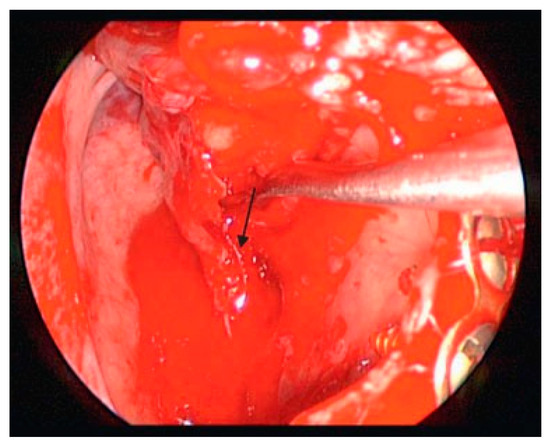

The techniques for endoscopic surgery are the same as for any open procedure, and the instrumentation for endoscopic techniques are frequently similar to open instruments. The main additions are the endoscopes, tower, camera and video monitors. The scopes today are typically Hopkins rods and come in different sizes (2.7 to 4 mm for head and neck purposes) and different angu- lations (0, 30, 45, and 70 degrees). The diameter of the glass rode can have a profound affect on the amount of light and visualization provided. The angle can also affect visualization. The camera is an industrial quality, 3-chip CCD (charge-coupled device), which is the type used for recording movie-quality videos. It is attached directly to the Hopkins rod and transmits the video signal to a tower. The tower has the printer, video equipment, light source, and monitor necessary to show the image to the surgeon. Figure 1, Figure 2 and Figure 3 show the typical instrumentation needed for any endoscopic case. For endoscopic orbital cases, the patient is into-bated and the head of the bed turned so the surgeon is on the patient’s right side. The video monitors are placed at the patient’s head for transantral orbital surgery and at the feet for endoscopic frontal sinus surgery. The gingivobuccal sulcus is then injected with local anes- thetic containing 1:100,000 epinephrine. This requires ~10 min to be maximally effective. Once the vaso-constriction is complete, a sulcus incision is made. The maxilla is stripped of periostium. Before beginning, we bend a plate for the end of the procedure. Then a 2-cm wide by 1-cm long Caldwell-Luc antrostomy is per- formed. We usually leave the bone as an osteoplastic flap for closure. Once the antrostomy is made, the intrasinus contents are cleared and decongested. After this is achieved, the nasal cavity is inspected. The roof of the sinus can now be visualized. If the patient has a trapdoor type fracture, the mucosal flaps can be raised and the bony fracture carefully opened so that the entrapped content can be replaced into the orbit. If the patient has a full-size defect, the opening should be inspected to ensure that none of the fragments are present within the orbital fat or in the inferior rectus muscle. Also of importance is the infraorbital nerve. It is extraorbital until the fissure is identified, and then it becomes intra- orbital. Care should be taken not to entrap this structure by the plating system. Figure 4, Figure 5 and Figure 6 show an antrum and the fracture in the floor.

Once the antrostomy is performed and the defect visualized, the scope is usually changed to a 30-degree scope and work on the fracture begins. The periorbita is left intact, the bone is stripped down, and the stable ledges are identified. The infraorbital nerve can also be identified.

Figure 5. Freeing up the periorbita and outlining the fracture.

Cmtr 02 00017 g005

Figure 6. Identifying the infraorbital nerve (arrow) with a freer.